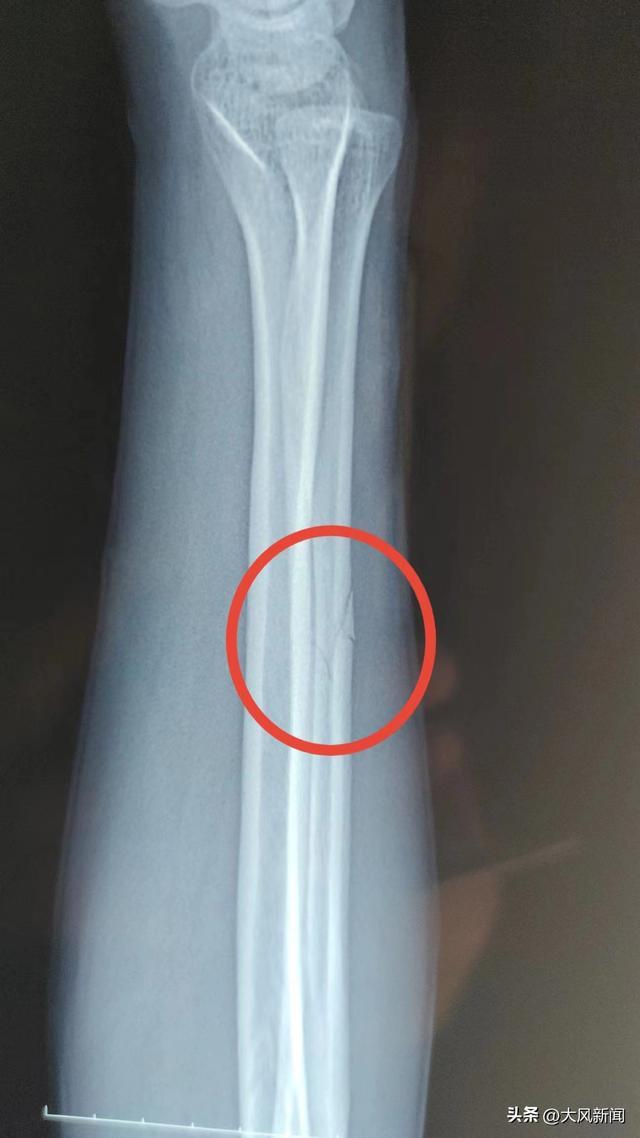

事发后,宋某报了警。当晚去医院检查,打了石膏后,医生让先回家观察观察。宋某系第二天右臂痛疼难忍,于2022年11月13日下午6时自行前往丹凤县医院检查。经诊断右尺骨骨折,外伤性头疼。

在宋某出院两个月后,2023年2月13日,商洛市丹凤县公安局龙驹寨派出所向宋某出具了第一次伤情鉴定报告。宋某人体损伤程度属于轻伤二级。